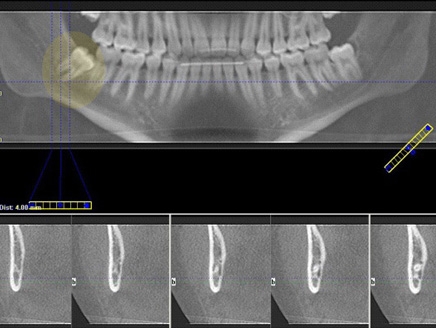

العربية : تبين أن الأشخاص الذين يجرون بانتظام صورا إشعاعية لأسنانهم هم أكثر عرضة من غيرهم للإصابة بأورام في الدماغ، بحسب دراسة أجراها باحثون أمريكيون نصحوا بتفادي إجراء هذه الصور كل سنة. ونُشرت الدراسة في مجلة "كانسر" الأمريكية وأجرتها إليزابيث كلاوي من جامعة يال بالاستناد إلى بيانات جمعتها من 1433 مريضا أمريكا تراوحت أعمارهم بين 20 و79 سنة ويعانون أوراما سحائية في الدماغ وهي أورام حميدة عادة.

وتبين أن المرضى الذين أجروا كل سنة صورة إشعاعية لأسنانهم وتعرضوا للأشعة السينية هم أكثر عرضة بمعدل 1,4 إلى 3 مرات للإصابة بورم سحائي من المرضى الآخرين وفقا لوكالة "فرانس برس".

وتعتمد نسبة انتشار الورم على سن المريض وعلى نوع الصورة الإشعاعية بما أن الأشعة السينية تستعمل بطرق مختلفة.